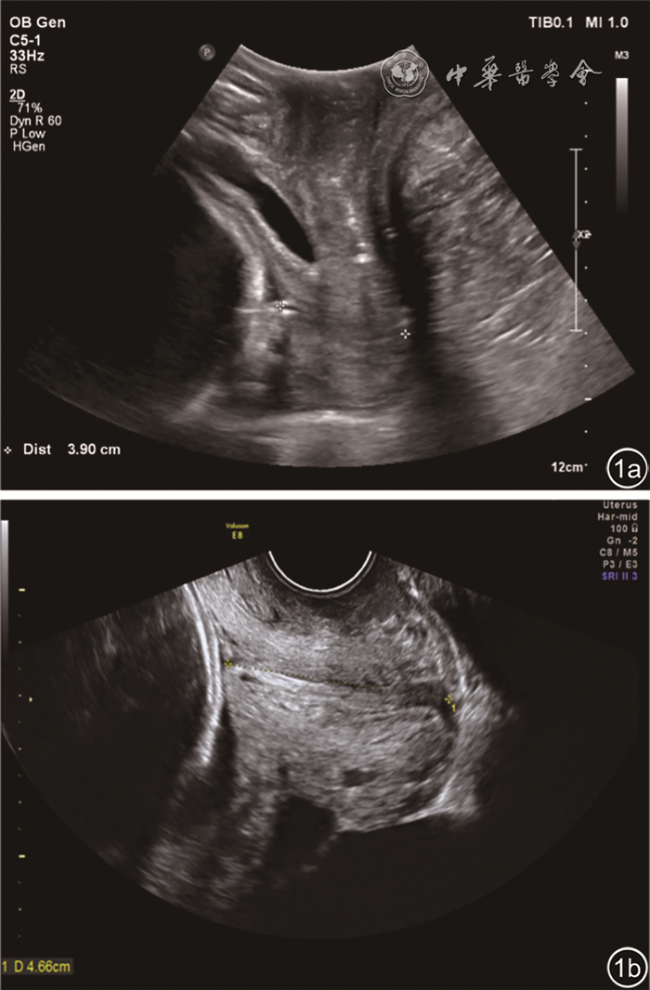

本研究评估标准参考加拿大妇产科医师协会母胎医学专业委员会的指南5:经会阴超声检查宫颈时,超声束沿阴道方向在矢状面上定向测量(图1),宫颈水平方向大致垂直于超声束,阴道几乎垂直。经阴道超声检查宫颈时,沿宫颈管最长径获取其长轴矢状切面,宫颈管、宫颈内口、宫颈外口均清晰显示(宫颈内口为平坦或V形凹槽、宫颈外口为凹陷或三角形的区域)。无论采取哪种检测方法,测量前均应寻找以下标记点:(1)宫颈内口;(2)宫颈外口;(3)矢状面可看到宫颈管全长;(4)子宫体;(5)宫颈与阴道交界处(可看到回声增高的界线)。前唇浆膜层到宫颈管距离等于后唇浆膜层到宫颈管距离。宫颈长度测量时应将卡尺放置于前唇/后唇接触宫颈的内口/外口处。当宫颈漏斗形成时,测量的宫颈长度应为闭合段宫颈长度。若宫颈弯曲时,测量的宫颈长度为宫颈内外口之间的直线、或分别测量多节段(≥2)再计算总和。有研究6表明当宫颈较短时,直线和多节段测量宫颈是否缩短时差异无统计学意义,因为宫颈较短时通常是笔直的。

图1 孕期宫颈超声检查。图a为经会阴超声检查,图b为经阴道超声检查